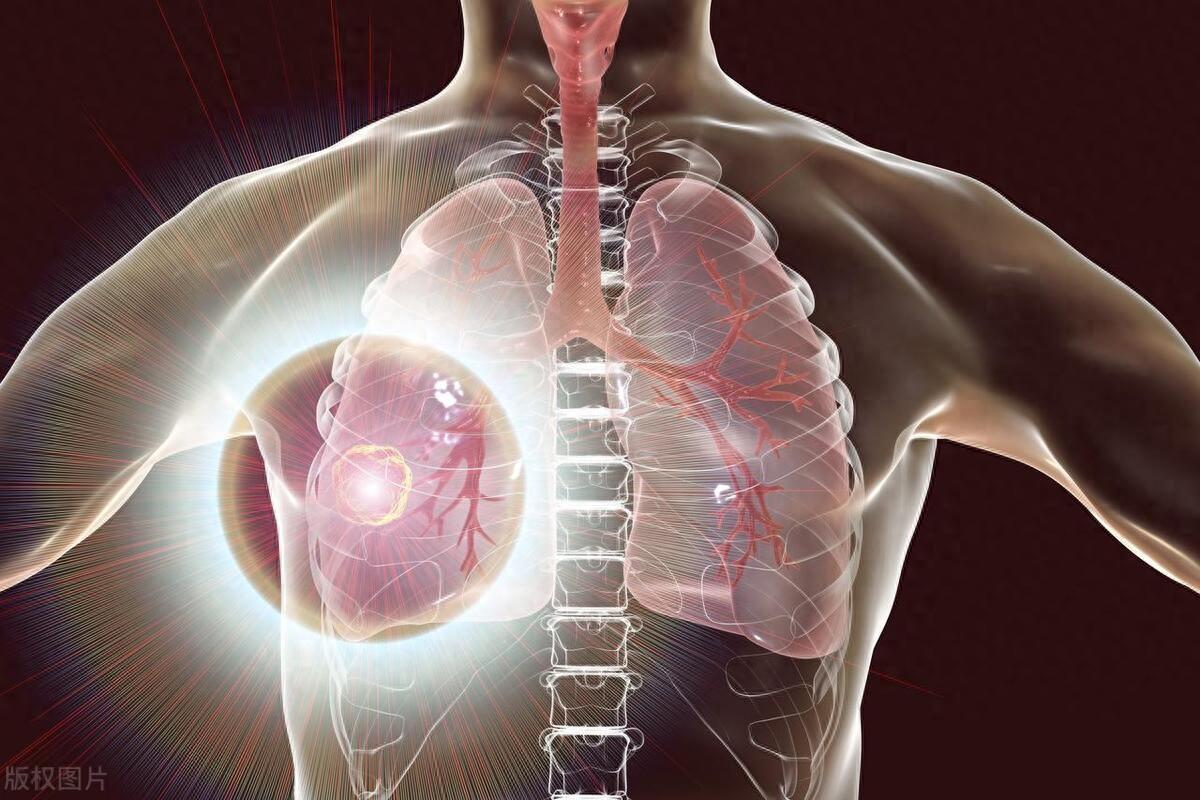

總之,肺癌的出現不僅與吸菸有關,還受到空氣污染和不健康生活習慣等多種因素的影響。雖然肺癌是一種複雜的疾病,但我們也可以通過控制自己的生活習慣、遵循健康的生活方式、進行篩查等方法來降低患癌的可能性。